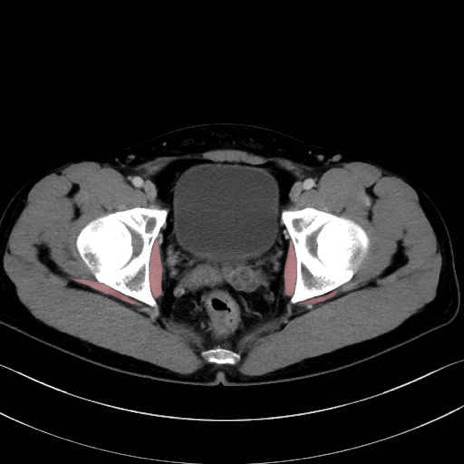

内閉鎖筋(obturator internus) のCT画像の解剖

内閉鎖筋 (Obturator internus)